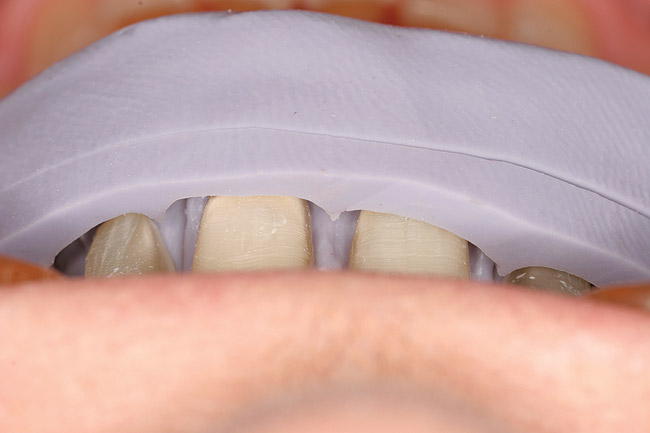

Figure 15  Reduction stents can be made to help ensure proper 3-plane reduction of maxillary anterior teeth. Under-reduction of the incisal third will often lead to edges too far to the facial. The laboratory becomes limited, and is forced to produce an over-contoured restoration.

Figure 15